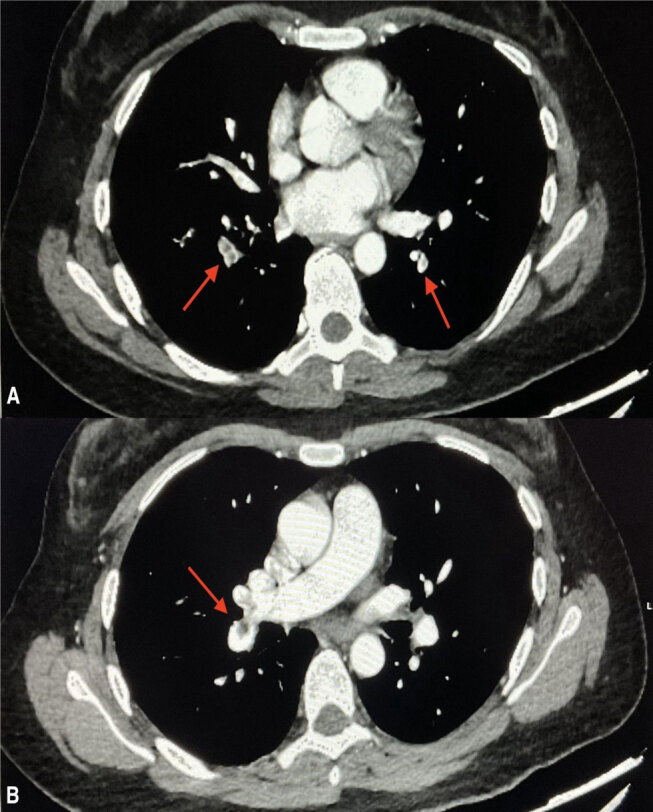

Abstract Image